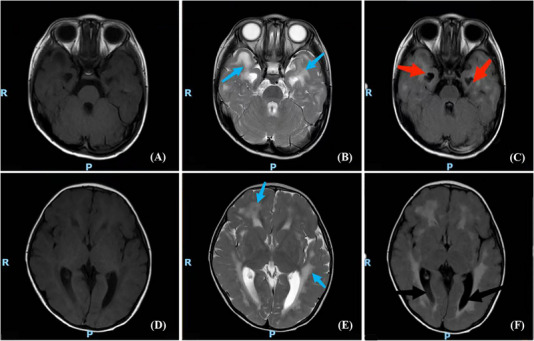

Results: A total of 15 patients was included, all presenting with various neurological symptoms, including developmental delay (100%), motor skill impairment (100%), language disability (78.6%), dystonia (93.3%), microcephaly (73.3%), sleep disorders (26.7%), regression (20.0%), vessel disease (6.7%), and epilepsy (6.7%). Neuroimaging revealed intracranial calcification (86.7%), cerebral atrophy (73.3%), and leukodystrophy (73.3%). Seven genes were identified, with TREX1 being the most common (40.0%, 6/15), followed by IFIH1 (20.0%, 3/15). Variant c.294dupA (p.C99Mfs*3) was detected in four unrelated patients, accounting for 66.7% (4/6) patients with the TREX1 variant. A literature review showed that TREX1 gene mutations in 35.6% (21/59) of AGS patients among the Chinese population.

Interpretation: Neurological symptoms are the most prevalent and severe presentation of AGS. Diagnosis may be considered when symptoms such as developmental delay, dystonia, microcephaly, brain calcification, and leukodystrophy emerge. TREX1 mutations are predominant in the Chinese population.